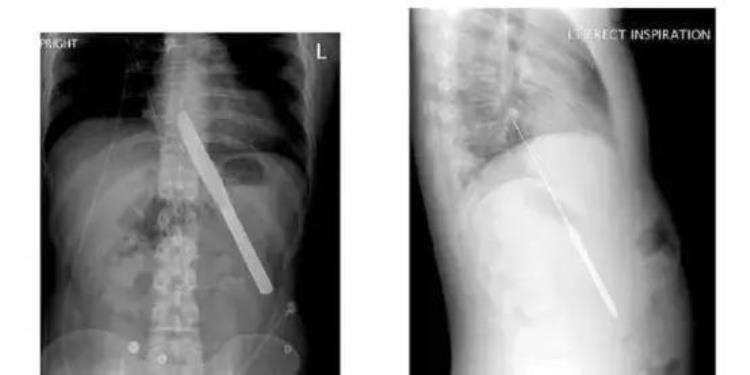

一把完整的西餐刀

一串磁铁珠子

一支完整的钢笔

牟主任表示,目前消化道异物的发生频率越来越高,吞进去的东西越来越五花八门。在就诊过程中,硬币 、纽扣 、电池 、玻璃等都是比较常见的消化道异物。